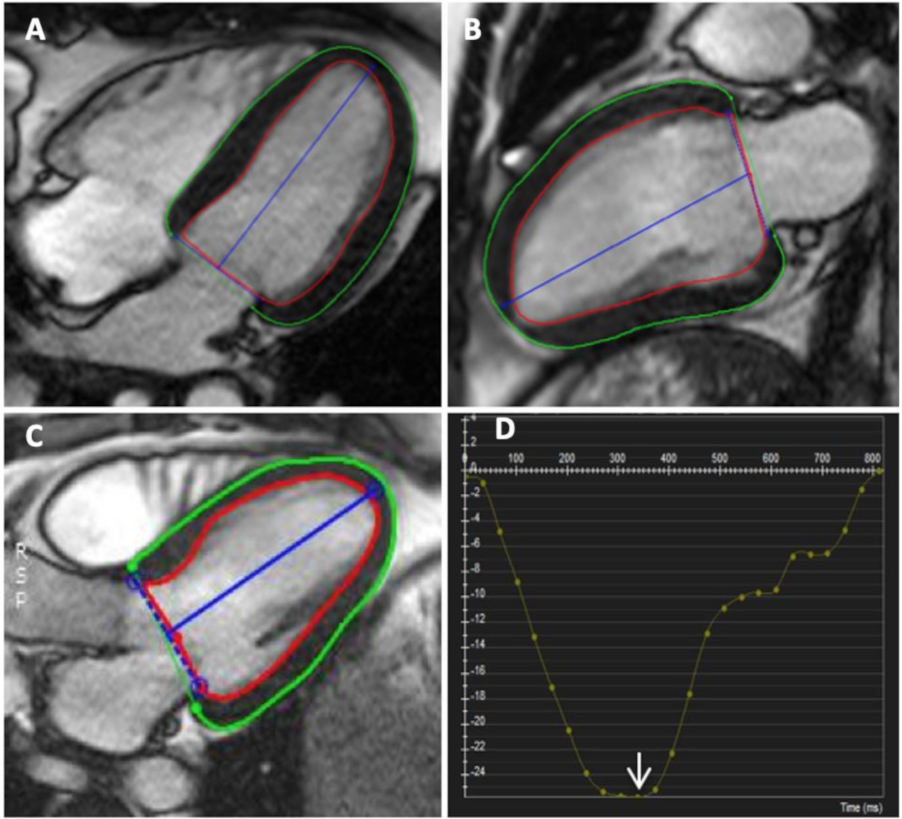

2.2. Cardiac MRI

5.2. Cardiac MRI